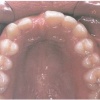

Ülemise hambakaare kitsenemine ehk tagumiste hammaste risthambumus

Hammustades on näha, et alumine hambakaar on laiem kui ülemine. Tagumine risthambumus võib olla kas mõlemapoolne või ühepoolne ja sageli hambakaarte keskjooned hammustades ei ühti. Tagumist risthambumust võib esineda 10...